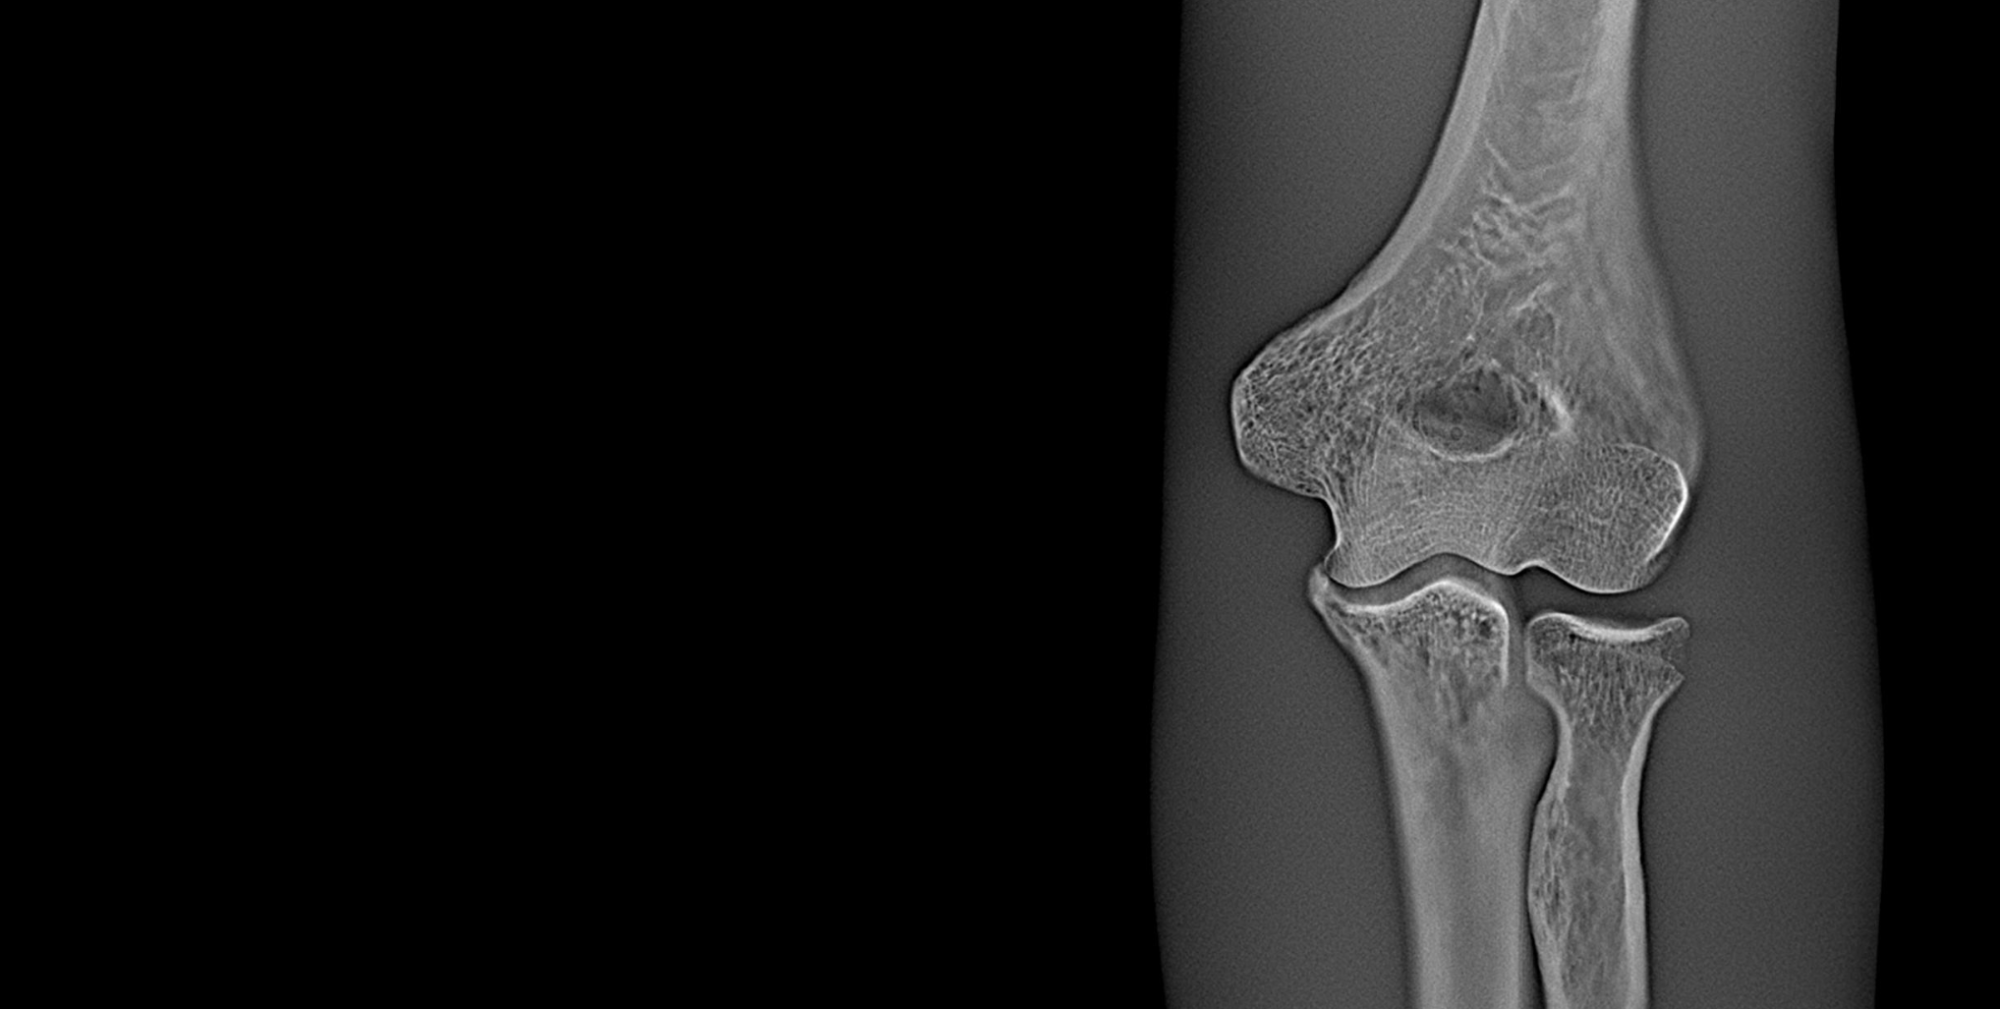

High-Quality Slices in Seconds.

Using novel image reconstruction techniques, enabling extremely quick analysis. The approach uses back projection together with a ramp-filter and is substantially less memory-intensive than other techniques that reconstruct the volume as a whole, such as CT.

With noise and artefact reduction techniques and the ability to reconstruct slices in super-resolution improve quality, while computational optimization ensures that the method is fast.